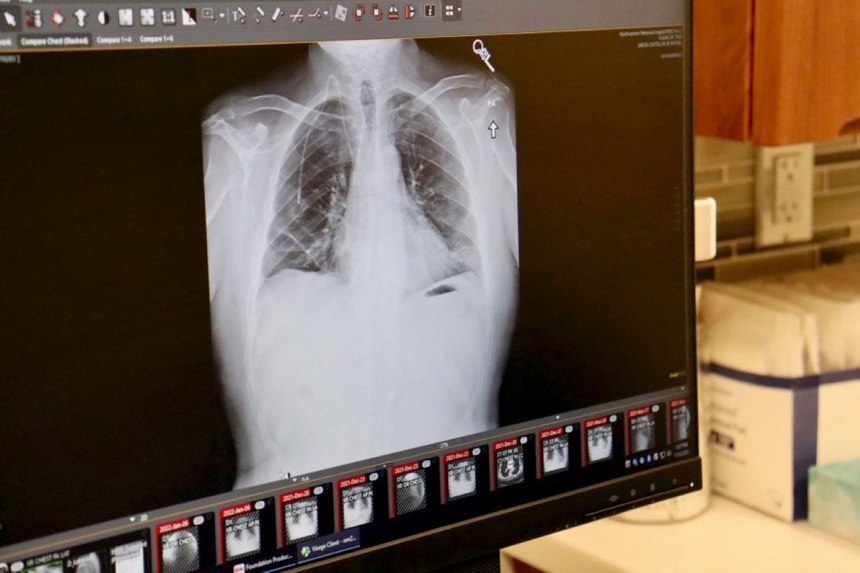

A pneumonia mata em média 16 pessoas por dia em Portugal, país que tem uma das mais elevadas taxas de mortalidade por pneumonia da Europa, alertou hoje a Sociedade Portuguesa de Pneumologia.

Em comunicado para assinalar o Dia Mundial da Pneumonia, que se celebra a 12 de novembro, a Sociedade Portuguesa de Pneumologia (SPP) adiantou que a pneumonia continua a ser a principal causa de mortalidade respiratória no país.

Segundo a mesma fonte, a doença é responsável por, "aproximadamente, 4,2% da mortalidade do país" e apresenta uma das taxas de mortalidade mais elevadas da Europa, "com valores superiores a 57 mortes por 100 mil habitantes".